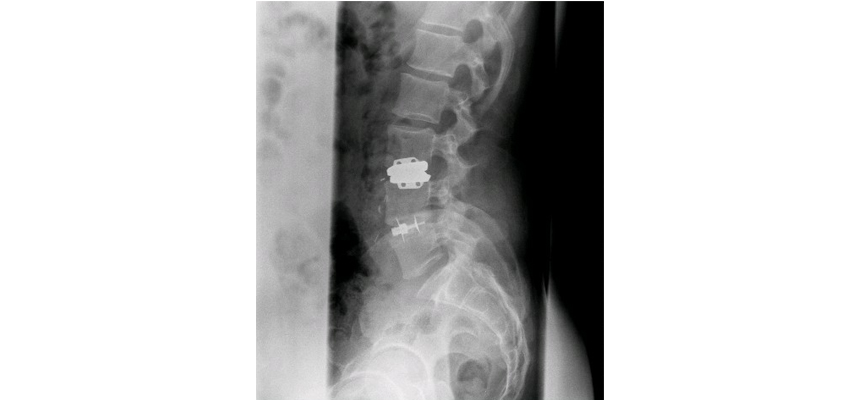

Alif Double Locking Cage A2L

Alif Double Locking Cage A2L® is part of a wide range of radiolucent cages equipped with a unique patented locking double blade mechanism, offering a variety of alternatives for the anterior surgery of lumbo-sacral spine.

The immediate and secondary stability of the cage is supported by simple rotation of instrument (UNIQUE CONCEPTION) which makes the two titanium blades penetrate into vertebral plates as soon as the instrument is turned.

The blades are completely integrated inside the cages.